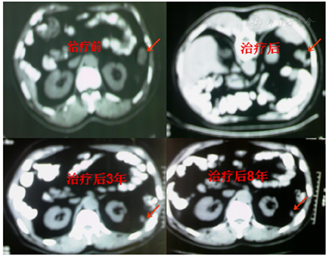

患者,男性,49岁。1998年2月23日,外科行结肠癌右半结肠切除术,术中见肿瘤位于回盲部约10 cm×5 cm×5 cm,侵出浆膜,质硬,术后病理:结肠低分化腺癌,侵及浆膜,肠旁淋巴结2/2转移(图1)。术后超分割放疗、增敏化疗、同步中药和生物制剂,至1999年11月复查4次,为稳定期,给予中药生物制剂维持治疗,2000年3月10复查,诊断脾区腹膜转移,给予三维适形放疗瘤内注射5-FU,同期中药和生物制剂。至2008年11月,8年复查16次,均为稳定期给予中药、生物制剂维持治疗。2012年6月11日,诊断颈淋巴结转移,采用了三维适形放疗,替加氟增敏化疗、中药、生物制剂综合治疗,中药生物制剂维持。2017年3月20日复查,卡氏评分100,稳定期,给予中药、生物制剂维持治疗。随访至2022年6月,术后生存24年,仍健在。

术后放疗、增敏化疗、中药生物制剂新综合治疗,下消化道急性放射反应2级。脾区腹膜转移灶治疗后1个月CT复查肿物大部缓解(PR),以后逐年缩小,治疗8年后仍可见14 mm×11 mm残留灶(图3),17年肿瘤完全缓解(CR)(图4),局部纤维化,未影响生活质量(图5),颈部淋巴结转移灶综合治疗后1个月为CR。CEA值接近了自己的正常值2.1ng/ml,3次以上检查的最低值视为该患者正常值,卡氏评分100(图6)。